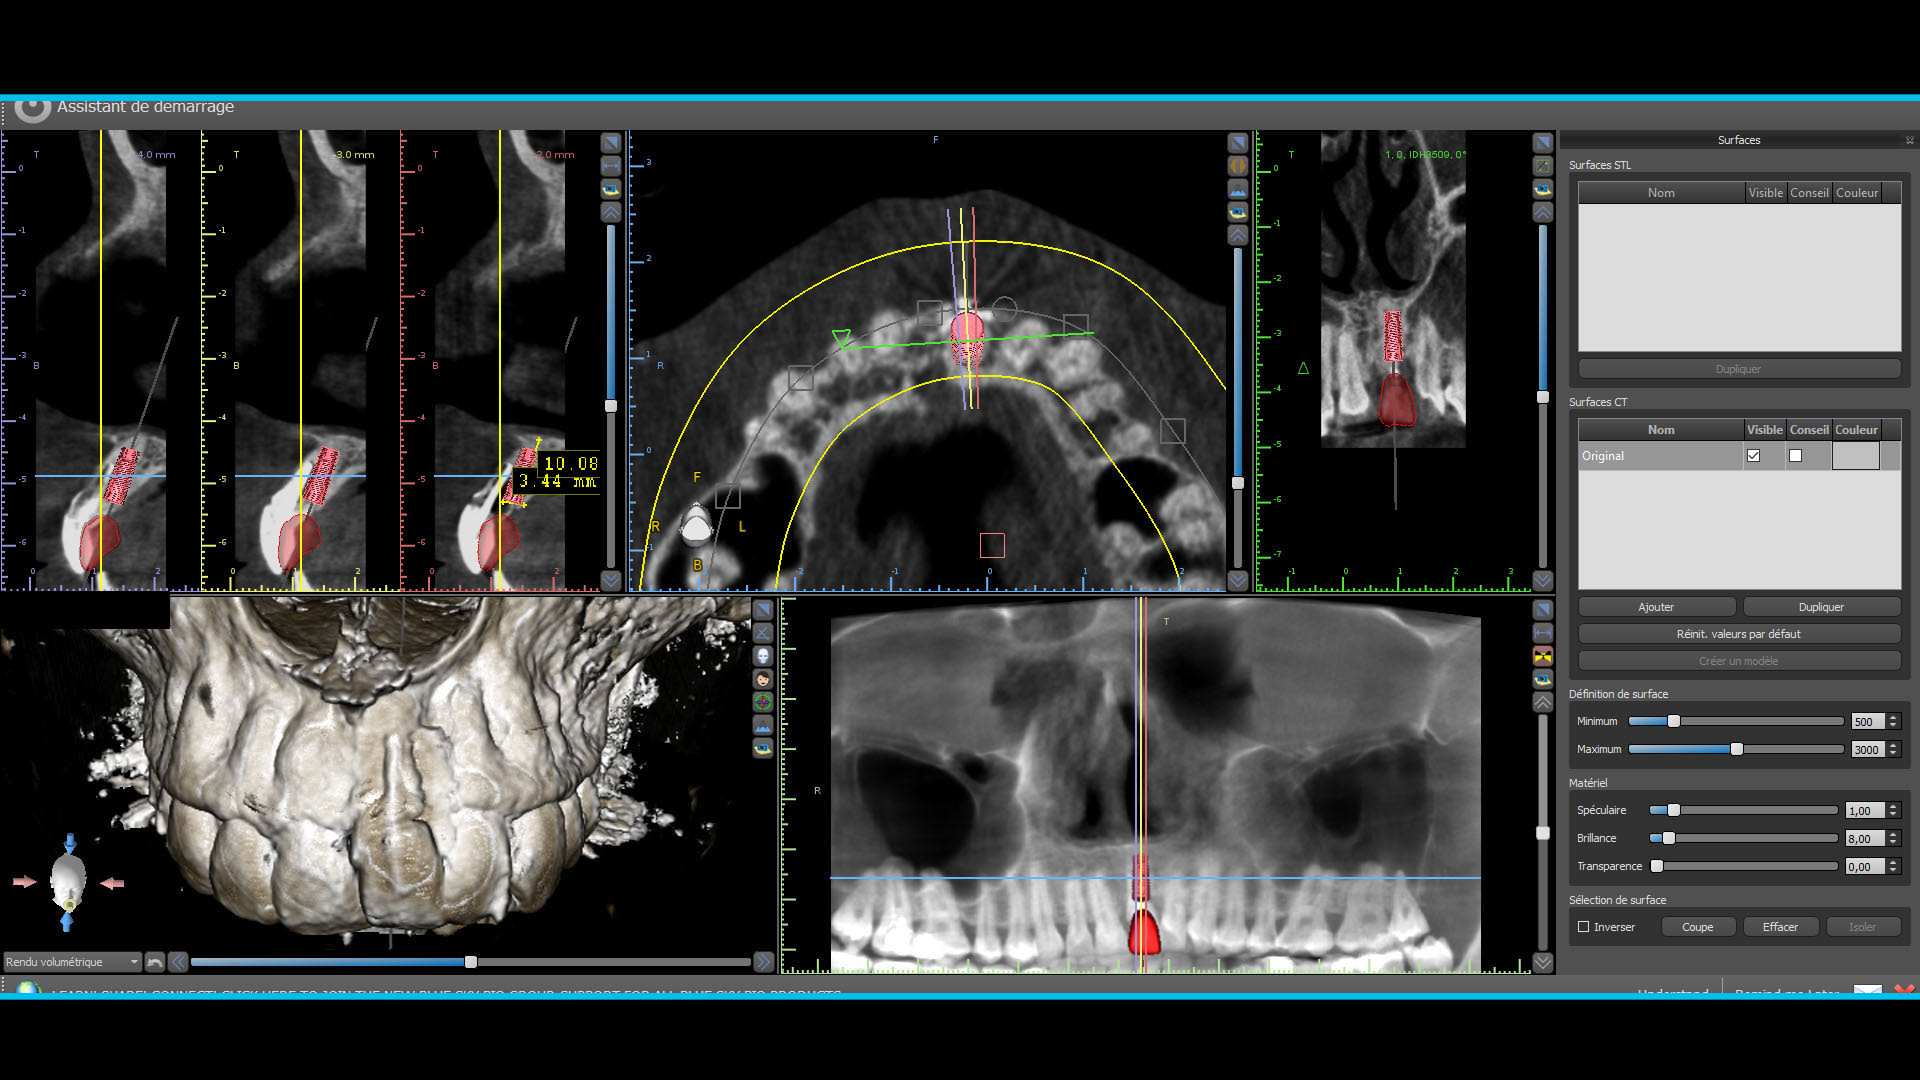

Quelques images du cone beam et de la planif

Planif 1 owxhvi - Eugenol

Planif 2 slmeas - Eugenol

Planif 3 v71j9j - Eugenol

Planif 4 my2dza - Eugenol

Planif 5 fqtf2p - Eugenol

Planif 6 ody3rj - Eugenol

Euh... ton implant est très très enfoui esthétiquement je pense que ça va pas être une super surprise (même si elle recouvre, pense que les patients regardent toujours en soulevant la lèvre...) ensuite par rapport à l'apex de ta 11 il semble très haut, je ferai une 3D perso pour voir mon plancher des fosses nasales.